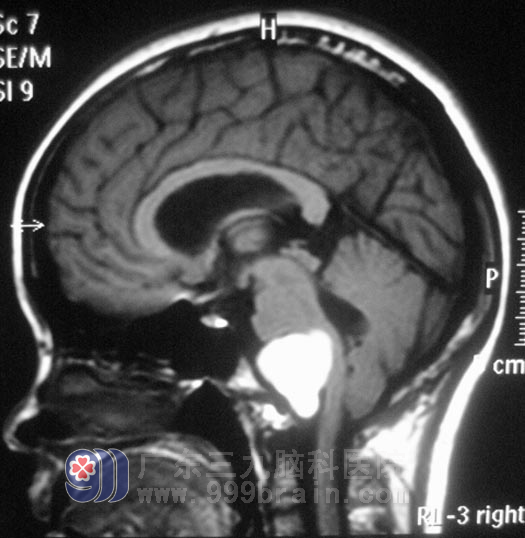

两周前,小凤出现了头痛、头晕,呈阵发性爆炸样疼痛及眩晕,一周前症状明显加重,伴恶心、间断呕吐,右下肢麻木加重。当地医院建议行颈椎MR检查,检查结果把医生都吓了一跳:小凤右侧延髓腹外侧有一占位,直径约2.7cm。在广东三九脑科医院复查MR,小凤延髓处肿瘤大小为4.19cm×2.63cm×3.74cm,伴有梗阻性脑积水,综合神经外科 鲁明主任初步考虑为胆脂瘤。